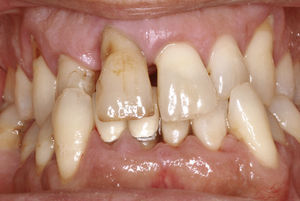

Se puede observar una tinción de color rojizo de la corona dentaria en las localizaciones muy hacia coronal y el defecto primario se puede sondar (fig. 10). Con frecuencia, los dientes afectados ofrecen un aspecto externo in- tacto, pero muestran una puerta de entrada situada en la zona proximal-cervical. El proceso evoluciona de forma asintomática y el diagnóstico suele ser un hallazgo radiográfico casual (figs. 9 y 11). La prueba de sensibilidad suele ser positiva y la prueba de percusión es negativa. Hay que hacer el diagnóstico diferencial con reabsorciones internas o externas y, en caso de defectos cervicales localizados, con una caries radicular.

Características radiográficasLas reabsorciones cervicales invasivas se caracterizan por los signos radiográficos siguientes:

Origen en el límite amelocementario.

Línea radioopaca alrededor de la luz del conducto (predentina).

Aspecto marmóreo del defecto.

Forma perimetral errática.

Orientación longitudinal.

Espacio periodontal continuo.